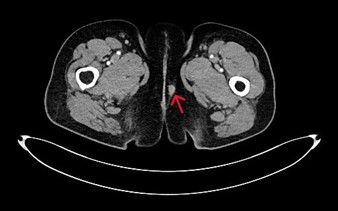

Three months after the liver resection, vulvar lesions appeared, and the patient was referred to the gynecology service. On physical examination, two firm masses were detected: one measuring 7 mm on the left labium majus and another measuring 15 mm near the left inguinal fold (Figure 1). The rest of the physical examination was unremarkable, and no inguinal lymph nodes were palpable. The histopathological results revealed infiltration by adenocarcinoma, likely of rectal origin, with an immunohistochemical profile of CK20+/CDX2+/CK7- (Figure 2). The extension study with a CT scan ruled out distant metastasis, identifying only the vulvar lesions (Figure 3). Consequently, the multidisciplinary tumor board recommended local resection of the tumor.

Figure 3: Initial vulvar metastasis in the left labium majus as seen on CT scan.